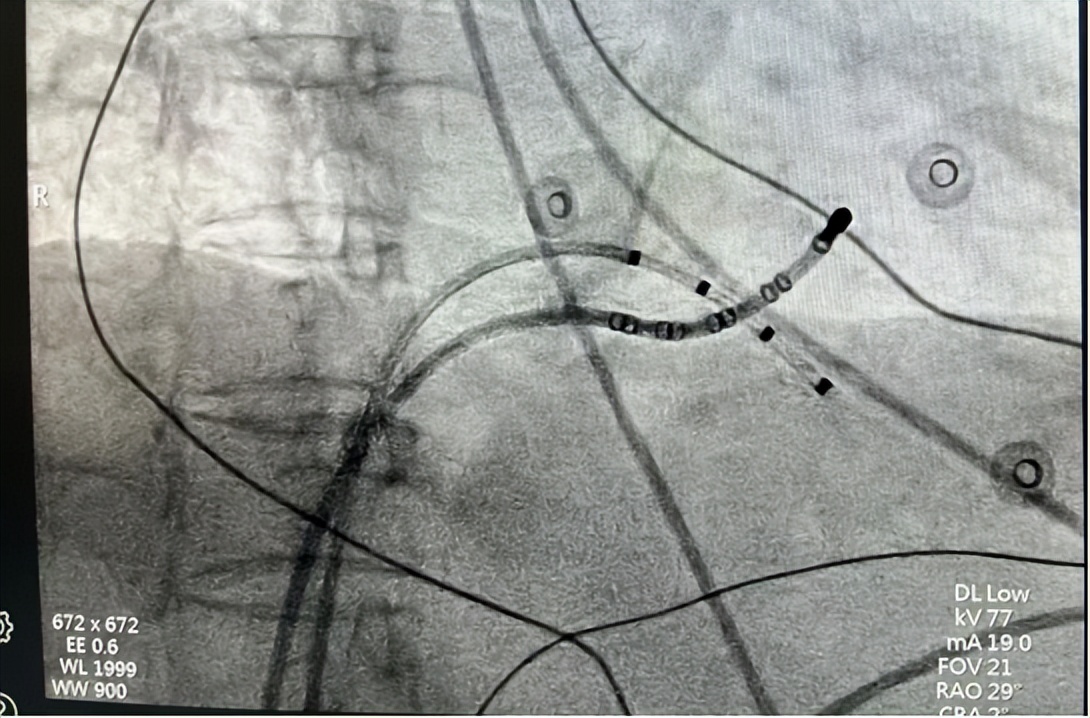

△术中导管放置